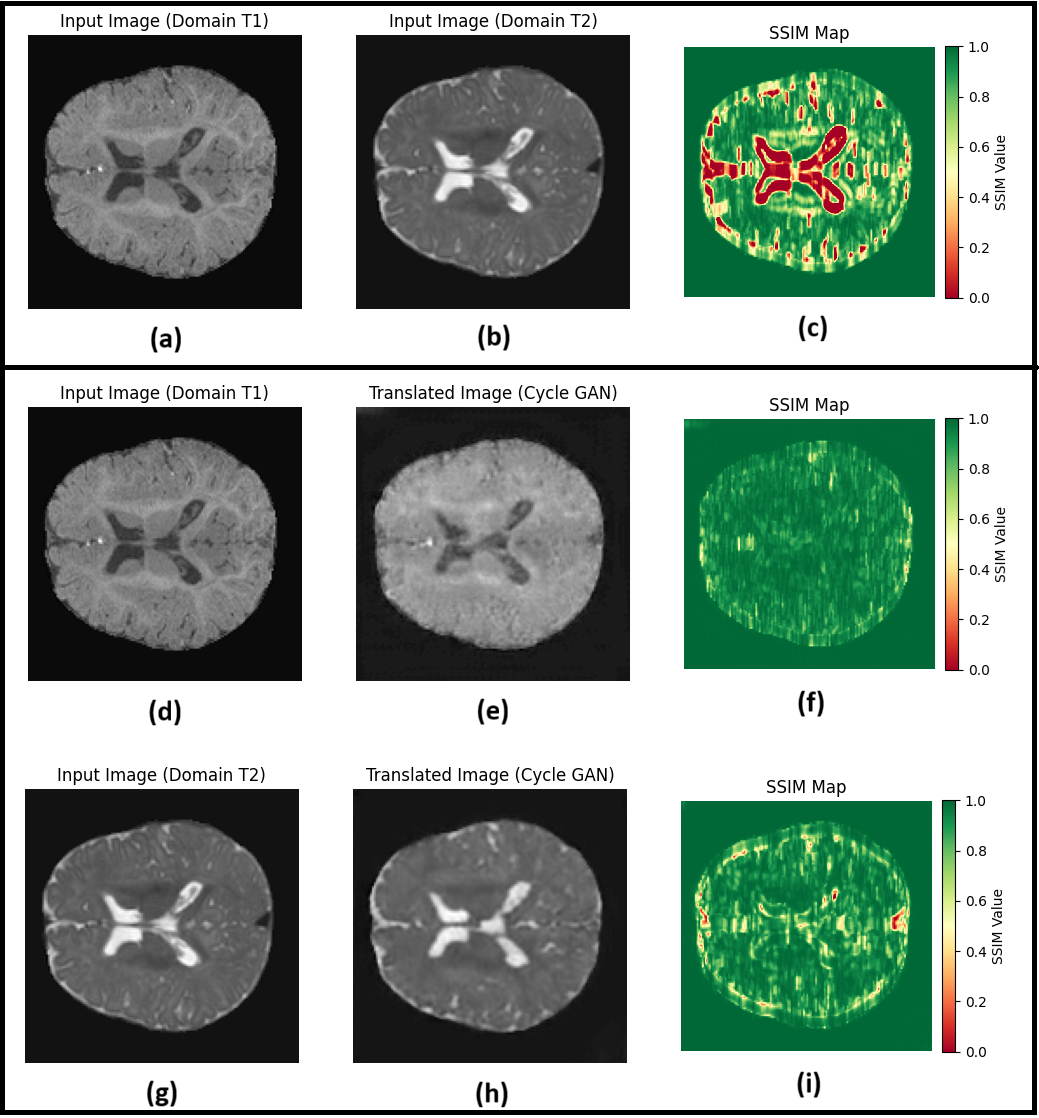

Refer to caption

Figure 5: SSIM map from original and generated T1 and T2 image by CycleGAN

Fig 4, 5, and 6 represent the analyses of domain adaptation using the structure similarity index measure (SSIM) between images of different domains. Fig 4(c), 5(c), and 6(c) represent the SSIM between the T1 and T2 modalities before translation. Fig 4(f) and Fig 4(i) represent the SSIM measure between T1 and translated T1, and T2 and translated T2, respectively, using BiGAN. It can be clearly seen that the structured similarity increased in 4(f) and 4(i) compared to 4(c). Furthermore, structural similarity was higher when translating T2 into T1 (SSIM value 0.945, fig 4(f)) than when translating T1 into T2 (SSIM value 0.909, fig 4(i)). Similarly, Fig 5(f) and 5(i) represent the SSIM measures between T1 and translated T1 and T2 and translated T2, respectively, using CycleGAN. It can be clearly seen that the structured similarity increased in Figs.5(f) and 5(i) compared to that in Fig.5(c). Furthermore, structural similarity was higher when translating T2 into T1 (SSIM value 0.960, fig 5(f)) than when translating T1 into T2 (SSIM value 0.934, fig 5(i)). Similarly, Fig 6(f) and 6(i) represent the SSIM measures between T1 and translated T1 and T2 and translated T2, respectively, using the proposed GAN. It is evident that the structured similarity increased in 6(f) and 6(i) compared to 6(c). Furthermore, the structural similarity was higher when translating T2 into T1 (SSIM value 0.960, fig 6(f)) than when translating T1 into T2 (SSIM value 0.933, fig 6(i)). Despite these differences, both translated modalities demonstrate substantial adaptation of images from one domain to another. The fine-tuning process, augmented by disparity and cycle consistency loss, enabled the model to maintain structural fidelity and anatomical realism, which was evident in visual assessments and structural similarity.